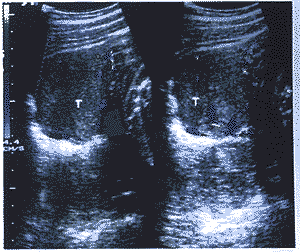

中国超声医学杂志990743 患者,女性,24岁。因怀孕后全身多毛、面貌改变26周入院。患者停经2个月左右出现 声音嘶哑,孕三个月左右出现痤疮、胡须、全身多毛。查体除上述表现外,尚可见皮肤色较 黑、乳晕不着色、腹无紫纹,考虑为雄激素增高所致。血激素检查:FSH 18.6mIU/ml, LH 180mIu/ml,PRL>200ng/ml,Ez>2000pg/ml,T>2000ng/dl,P>100ng/ml,即T(雄 激素)明显增高,应用Domier AI-5200型彩多普勒超声诊断仪,探头频率为5MHz,超声检查 表现:耻上见胎头,双顶径73mm,见胎心胎动,股骨长53mm,胎盘位于后壁,厚28mm,羊水 最大前后径50mm。子宫右侧附件区见50mm×52mm×65mm稍强实质肿块回声,边界清,有包膜 ,内回声欠均匀(图1),左侧附件区未见明显肿块回声。CDFI:胎儿脐带血流A/B比值为3.8 ,右侧附件肿块周边及内部均见丰富的彩色血流,呈红蓝相间的点、条状彩色血流回声(图2 ),肿块一动脉频谱为Vmax 55cm/s,Vmin 31cm/s,RI 0.43,为高速低阻血流(图3)。超声 提示:1.右侧附件实质性肿块(具分泌功能之卵巢肿瘤);2.单胎头位。患者继续怀孕至38 W+2天,行剖腹产及卵巢肿瘤切除术,剖出一正常男婴,出生时有轻度窒息,羊水 过少。术中见右卵巢肿瘤大小6cm×5cm×4cm,包膜完整,质硬。病理诊断:(右)附件卵巢 支持-间质细胞瘤(高、中度分化)。肿瘤部分区域瘤组织呈腺瘤状结构,衬以葵花子样核的 支持细胞,大部分区域呈片状排列的间质细胞。

图2 肿块血流供应非常丰富,呈红蓝相

间的点、带状彩色血流信号